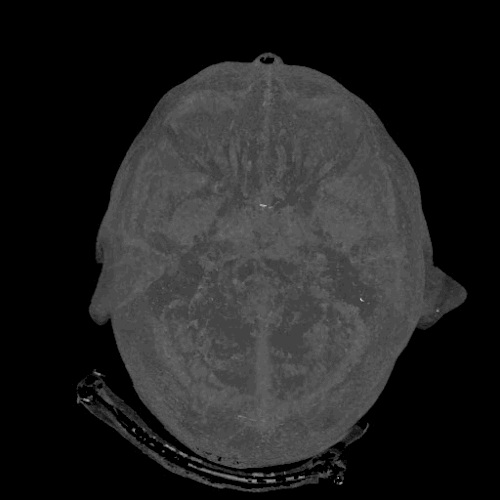

1. Bộ não của chúng ta là bộ nhớ có dung lượng lớn nhất thế giới

Bộ não có thể ghi nhớ đén 2,5 triệu GB thông tin, tức là khoảng 300 năm video. Đỉnh cao của khả năng ghi nhớ xảy ra ở tuổi 25 và bắt đầu giảm ở tuổi 50, trừ khi bạn huấn luyện lại bộ não của mình.